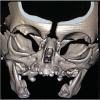

Introduction: Nasal obstruction is an important condition that can lead to severe respiratory distress in newborns. There are several differential diagnoses, and one of them is congenital nasal pyriform aperture stenosis (CNPAS). CNPAS is a rare case of respiratory distress caused by excessive growth of the nasal process of the maxilla and leads to narrowing of the anterior third of the nasal cavity. Diagnosis, associated anomalies, and treatment strategies are reviewed by the following presentation of two cases.

Case presentation: We report two cases of infants diagnosed with CNPAS. The patients in the first case had no concomitant comorbidities, and the outcome was successful after surgical correction of stenosis. The patient in the second case had an associated holoprosencephaly, and although surgical correction and nasal cavity patency, the patient remains dependent on tracheostomy due to dysphagia and neurologic impairment.

Discussion: Airway obstruction affects 1 in 5000 children, and CNPAS is a diagnosis frequently forgotten and even unknown to neonatal and pediatric intensivists. Newborns are obligate nasal breathers, and, nasal obstruction, therefore, can lead to severe respiratory distress. CNPAS is not only rare but, many times, is not easily recognized. It is important to bear in mind the diagnostic criteria when evaluating infants with nasal obstruction. Conservative treatment should be prioritized, but surgical treatment is required in severe cases with failure to thrive and persistent respiratory distress. Respiratory distress and dysphagia may persist to some degree despite correction of the stenotic pyriform aperture due to associated narrowing of the entire nasal cavity and association with other anomalies. Final Comments: CNPAS is a rare condition and may be lethal in newborns. Differential diagnosis of nasal obstruction must be remembered to recognize this anomaly, and the otolaryngologist must be familiarized with this condition and its diagnosis. Precise surgical treatment in severe cases have high rates of success in children without other comorbidities.